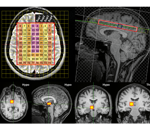

Study links brain temperature with survival after traumatic brain injury